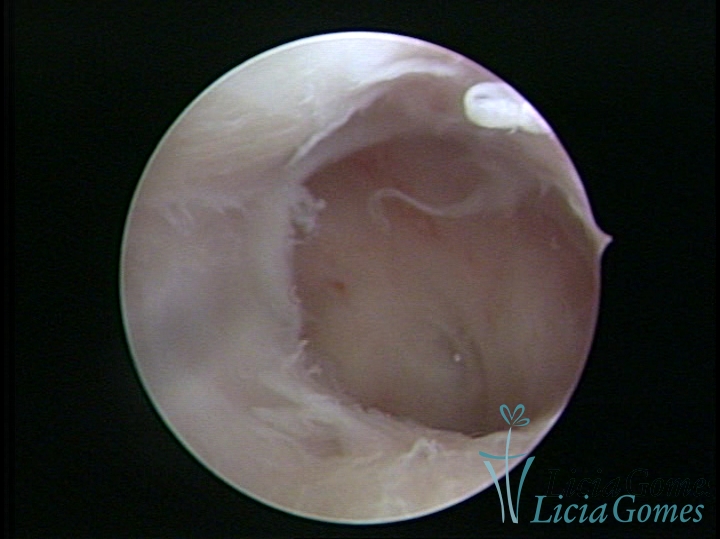

• SINÉQUIA TIPO FIBROSA